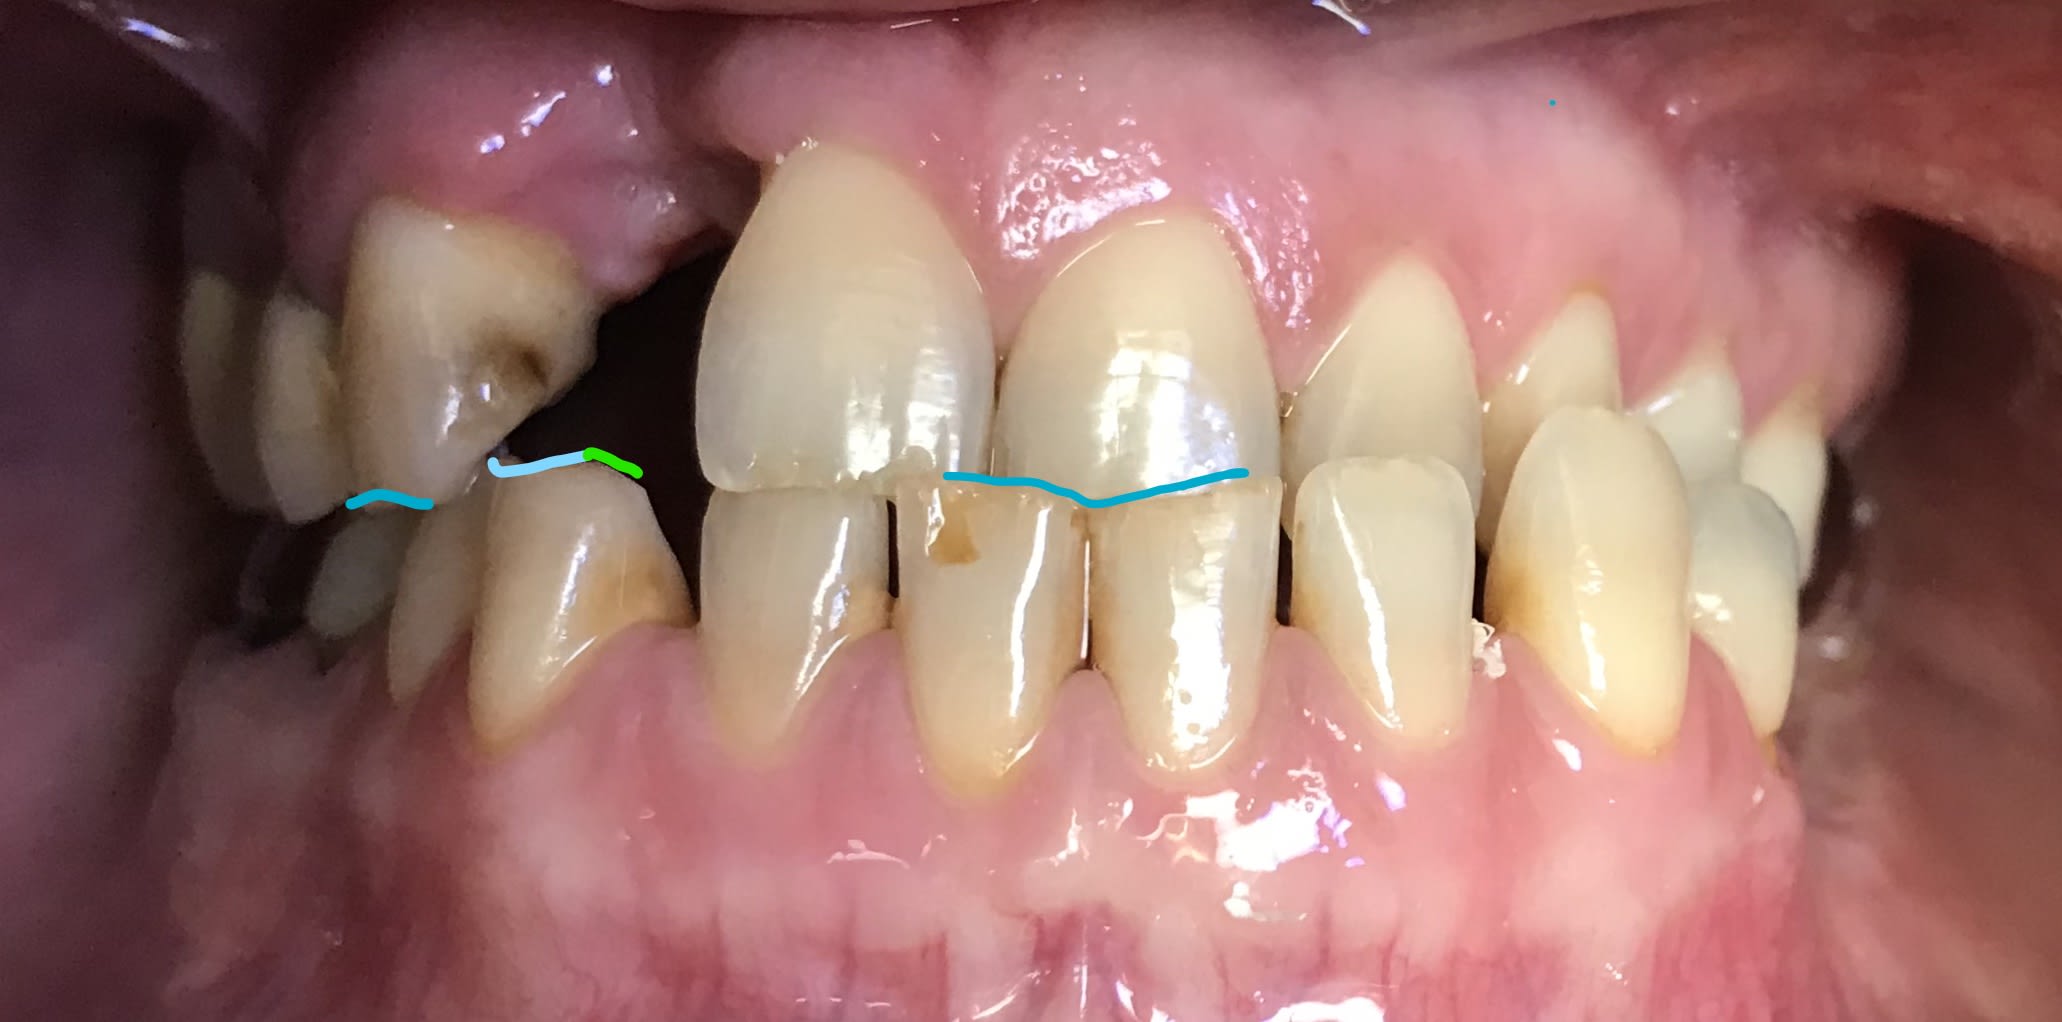

> Tu me conseilles quoi pour ce cas ?

Oui je fais un implant sur la latérale et un appareil à la mandibule

Elle a la gueule de travers . Donc faut bien lui replacer tout ça avant ... c’est pour ça que j’attendais qu’Enlaye nous fasse un petit topo.

Junior faudra que tu fasses gaffe à 1 truc , quand meme :

à la couronne metal du fond en bas à gauche ( 37?).

tu vas la garder pour mettre un crochet , je suppose , mais saches quand meme . que ç est elle qui a mis le bordel .

elle doit gêner en RETROpropulsion laterale çàd en fermeture alors qu'il est couché coté droit ,par exemple et un peu en propulsion aussi . pas pour rien qu'il ait perdu sa 12 .

donc tu la ( 37?) racles bien en mesial lingual et plus si affinité .

tu la transformes en bite d'amarrage .

et bien sur SURTOUT PAS de taquet dessus !!!.

et la 12 qui est à la croisée des chemins , j'y mettrais un prov sur l'implant avant de mettre la définitive pendant 2 mois facile .

quant à l'appareil il ne devrait pas trop poser de pb , puiqu'il ne servira à rien ( d'un point de vue occlusal ) .

plus sérieusement, à part la 37 que je retouche.

Y a moyen de faire autre chose ?

Avec sa classe 3 squelettique , sa canine va taper pile poile sur le bord libre de la couronne sur Implant si je pose un implant !